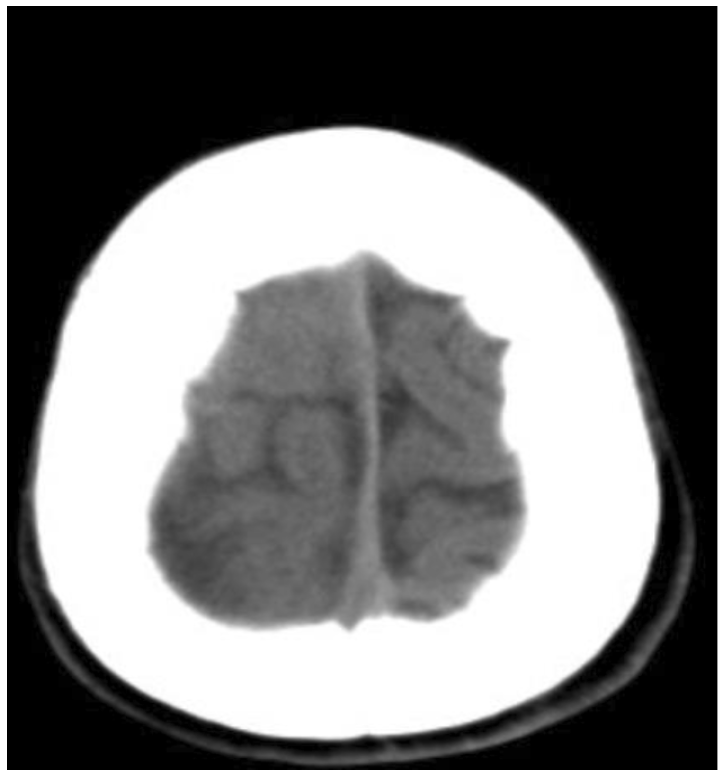

此病童的電腦影像,電腦斷層影像(非注射對比顯影劑),在冠狀切面(圖一)清楚呈現顏面部上頜竇(maxillary sinus)、鼻腔、篩竇(ethmoid sinus)、蝶竇(sphenoid sinus)等腫脹與不均值等病灶,且與健側對照,佐以軸狀切面影像,額竇(frontal sinus)的腫脹與不均值密度病灶(圖二)能較清楚呈現。進一步思考,病童呈現“雙眼球無法往左側移動”“頭痛且意識狀況異常”等,循著解剖器官組織的概念,審視眼部的影像,右眼框骨頭附近篩竇組織腫脹(圖一),審視腦部的影像,不管是軸狀面或是冠狀面影像(圖三),腦部組織腫脹且“推擠”至左側腦部呈現中線偏移。在部分腦部頂葉(parietal lobe)的影像(圖四),呈現相較低密度的“液體”狀成像,結合病童病史和抽血報告,積液部分疑似蓄膿,鑑別診斷可與慢性出血的稍高或等值密度做解析。另外,亦可藉由電腦軟體上可顯示的”Hounsfield unit, HU” 進行分析解讀。

圖三(之1)、頭部電腦斷層軸狀切面(axial view)(左圖)和冠狀切面(coronal view)(右圖):右側腦部呈現明顯腫脹,中線往左側偏移(橘紅色箭頭),右側側腦室(藍色星星)被擠壓,側角結構都已不見。

圖三(之2)軸狀切面(axial view):對比左側腦實質,右側腦實質和腦迴明顯腫脹,白質和灰質之間界限模糊。